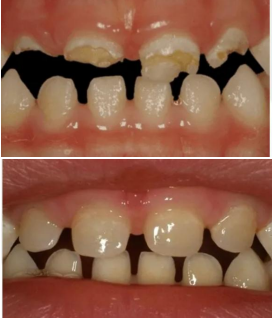

CARIE NEI BAMBINI E CURA DELLA MALATTIA CARIOSA

La carie nei bambini è una patologia molto diffusa e, se trascurata, può causare dolore e complicazioni future. Nel nostro studio di Bologna trattiamo la malattia cariosa nei bambini con tecniche conservative e minimamente invasive, adatte anche ai pazienti più piccoli. Ogni trattamento viene eseguito con la massima attenzione, spiegando ogni passaggio al bambino per ridurre ansia e paura del dentista.